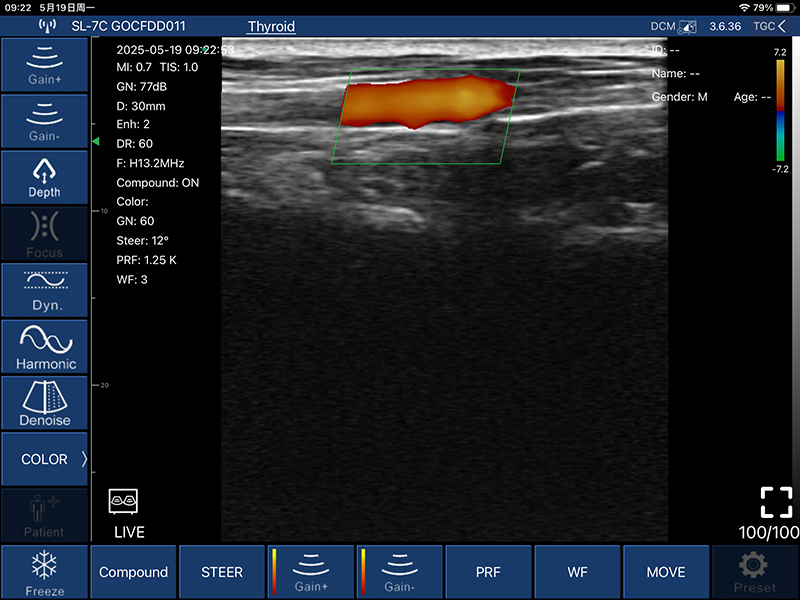

• 显示模式:B、B/M、COLOR、PDI、PW

• COLOR模式:

偏转角度:-12/-7/0/7/12度

PRF:≧4组

壁滤波: 0-15

彩色增益:0-100